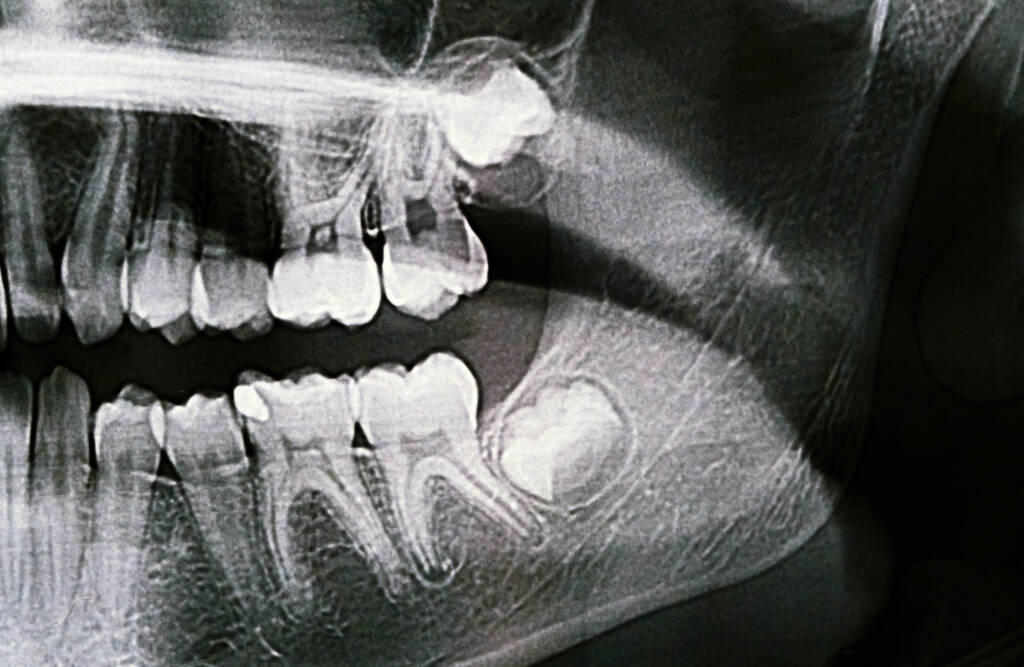

臨床 X 光片示範:橫生智慧齒嚴重壓迫前方臼齒

情況一:橫向阻生 (Horizontal Impaction)

這是臨床上最常見且棘手的情況。智慧齒呈「水平」方向生長,牙冠直接頂住前方的臼齒。這種結構就像一顆定時炸彈,長遠會持續推擠牙列,甚至導致劇烈疼痛及牙根吸收。

情況三:導致鄰牙不可逆的蛀蝕

這是 Jessie 特別強調的重點風險。傾斜生長的智慧齒會與前方的第二臼齒形成夾角,極易藏污納垢。往往當患者感到疼痛時,前方健康的第二臼齒已被蛀壞。由於該位置極難進行補牙或杜牙根,最終可能導致**「為了保命,兩顆牙齒必須同時拔除」**的慘痛後果。